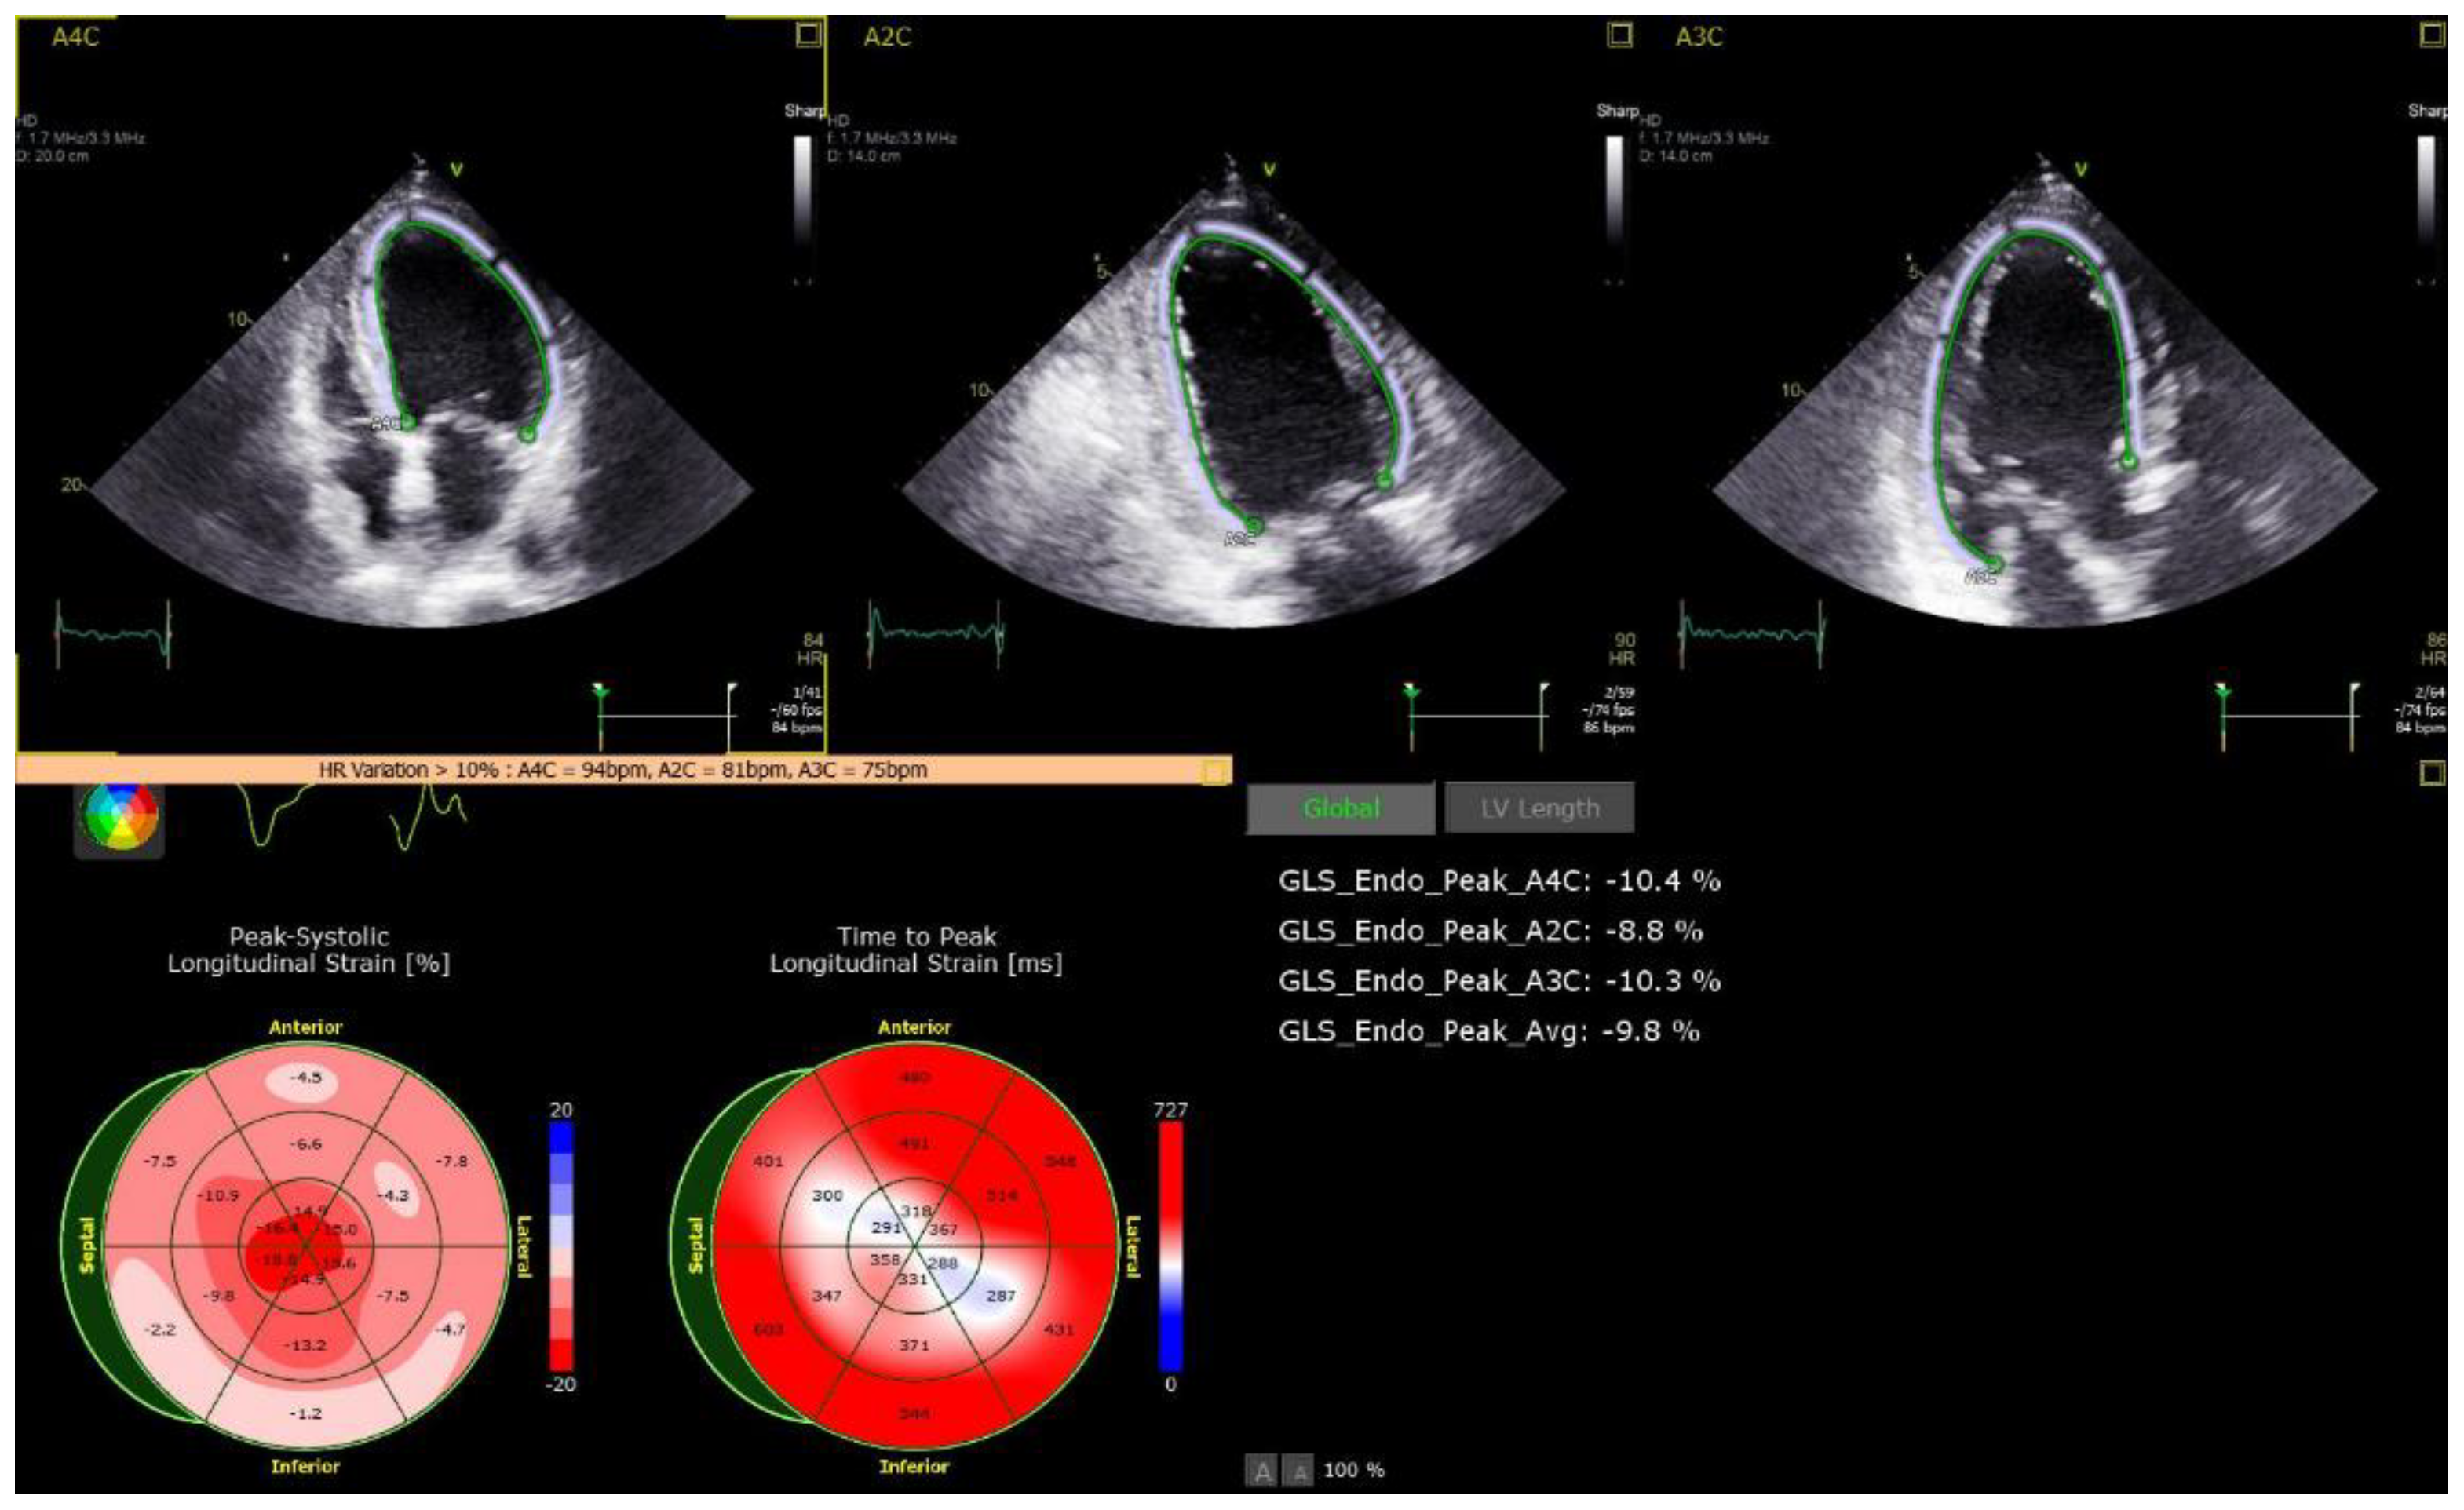

| Speckle Strain | ||||

| LV GLS (%), mean (SD) | 13 (±5) | 17 (±2) | 18 (±4) | 0.016 |